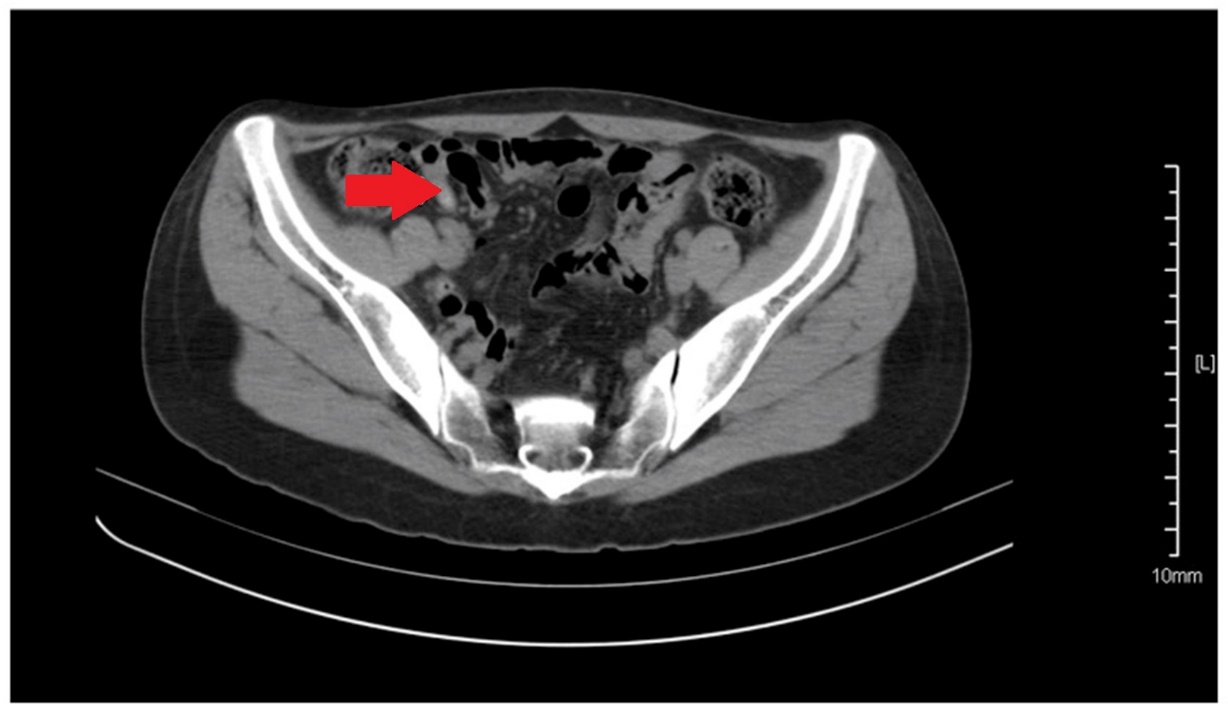

CT κοιλίας. Κόκκινο βέλος — Τυφλίτιδα. Σημαντική πάχυνση τοιχώματος τυφλού (Ευγενική παραχώρηση Dr. V. Penopoulos)